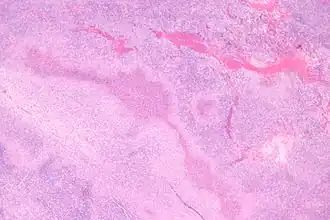

La biopsie ganglionnaire permet, outre la recherche de la bactérie ou de son ADN, de faire une analyse anatomopathologique de ce dernier[14].